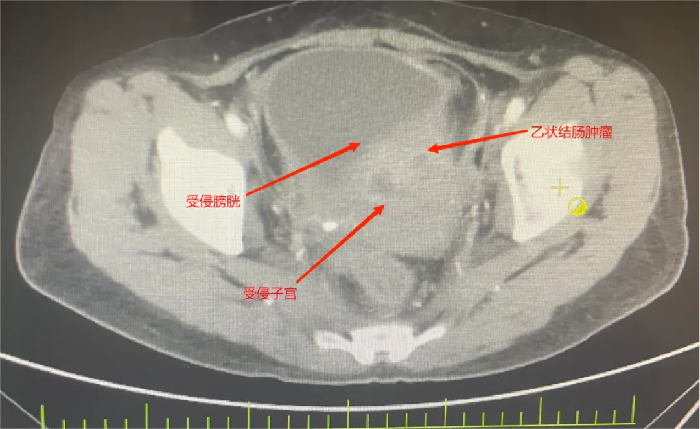

她被确诊为乙状结肠癌,肿瘤已“疯狂”侵犯膀胱、子宫、输尿管等多个盆腔脏器,还伴随不全性肠梗阻。2个月前在外院住院治疗,因手术风险大,外院仅为她做了横结肠造口术缓解梗阻,可术后不幸出现结肠膀胱瘘——小便中混着大便的症状让她痛苦不堪,叠加尿路感染、肿瘤引发的消化道出血,以及尿路梗阻导致的肾功能不全,多重并发症叠加,生活质量跌至谷底。

先是完整切除受肿瘤侵犯的直肠与乙状结肠原发灶,紧接着剥离与肿瘤紧密粘连的子宫及双侧附件并完整移除,随后小心翼翼分离膀胱与周围组织,将受侵膀胱全部切除——前三项切除手术已耗极大精力,团队仍需在腹腔镜下用回肠精心构建新的膀胱通路,确保患者术后排尿功能正常。

8小时不间断操作,一台集“腹腔镜下根治性直肠前切除术+改良广泛全子宫切除+双侧附件切除+全膀胱切除+回肠代膀胱术”于一体的超大型联合手术终于顺利完成。